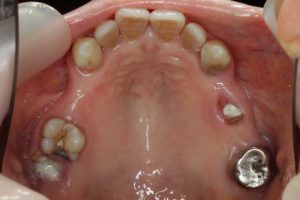

- 術前

- 術後

- インプラント手術直後のレントゲン

長い間お疲れさまでした。この方は、前歯に審美的なインプラントを入れるため、抜歯後4ヶ月待ち、仮歯で歯肉が成熟するのを数が月待っていたりした為に、完成まで時間がかかってしまいました。

虫歯治療などは短期間で終えることができるのですが、歯ぐきをいじり出すとどうしても治癒期間が必要となり長くなってしまいます。それもこれも奇麗な仕上がりのために欠くことのできないものです。何卒ご容赦を!